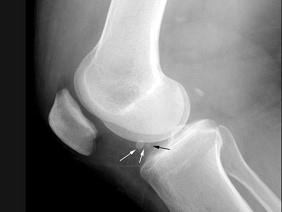

问题 女,65岁,右膝痛,活动受限,结合图像,最可能的诊断是?(?)

选项 A.神经性关节病 B.创伤性关节炎 C.退行性骨关节病 D.类风湿关节炎 E.痛风

答案 C